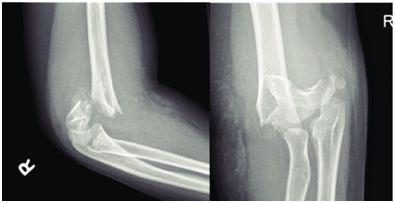

4.屈曲型

多系肘关节屈曲位,肘后着地,尺骨鹰嘴直接撞击肱骨髁部,使髁上部骨折。骨折远侧段向前移位,近侧段骨端向后移位。骨折线自前上方斜向后下方。

3.在严重移位的骨折中,肘前皮肤常出现广泛的瘀斑,软组织肿胀和皮肤褶皱。部分骨折可出现患肢“S”形畸形。

1.体格检查:压痛明显,仅限于肱骨髁上活动受限,肘后三角关系正常。

2.X线检查:可见骨折线。